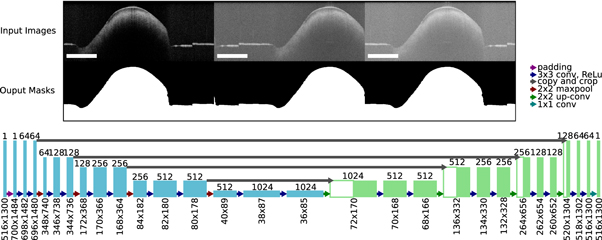

The binary masks were generated from each OCT volume by using a deep neural network with U-Net architecture (figure 5). The U-Net was introduced by Ronnenberger et al and is used for semantic image segmentation (Ronneberger et al

2015). The advantage of the neural network compared to usually used minimal path search algorithms is that it can adapt better to artefacts (e.g. reflections). The U-Net architecture used for this work was very close to the original publication, only the input and output size was changed to match the size of the OCT images, which had an input size of 516 × 1300 pixel. Each input image was extrapolated by mirroring to a size of 700 × 1484, so that the output size matches the original image before the padding. As a training dataset, 1700 (arbitrarily chosen) images from each OCT system were extracted from the OCT volumes of 80 different samples. A ground truth segmentation was created by manually segmenting the images into foreground and background. For the training the dataset was divided into training (80%) and test data (20%). 25% of the training data was used as validation data during the training. The split of the dataset was between the samples in order to assure that images from the same sample were only present in one sub-dataset to reduce overfitting. During each training step random data augmentation was applied to the OCT images. The data augmentation involved a random adjustment of the contrast and a random horizontal shift of the image content. This was done in order reduce the chance of overfitting and to improve the generalization of the U-Net. The training was performed for 300 epochs. For the optimization an Adam-optimizer with a learning rate of 0.000 001. The loss function was defined as the sum of the binary cross entropy Lce

and the dice loss Ld

(Ronneberger et al

2015, Milletari et al

2016, Taghanaki et al

2019). It combines the advantages of the dice loss to give valid results for imbalanced segmentations problems, where one class is under represented and the cross entropy, which focusses on the penalization of false positives and false negative segmentations (Taghanaki et al

2019). The cross entropy was calculated for each pixel of the OCT image, while the dice loss was determined as a scalar value for each image. So the loss function L combines local and global metrics. p(i) is the binary ground truth and  is the prediction between 0 and 1. N is the number of pixels in the mask, the pixel is defined by i.

is the prediction between 0 and 1. N is the number of pixels in the mask, the pixel is defined by i.

Figure 5. Overview of the configuration of the U-Net used to create the binary masks from OCT images. Examples of input OCT images with the used data augmentation and the corresponding output masks used to train the network (top). Architecture of the U-Net in order to process the OCT images. The rectangle in the bottom left of each image has the length of 1 mm.

Download figure:

Standard image High-resolution imageThe resulting affine transformation T2 was then applied to the cutting lines Csd of the SD-OCT to complete the transformation onto the SS-OCT. An example for a successful registration is shown in figure 4. The histological section and the corresponding OCT B-scans were extracted along the same 'cutting line'. The green and yellow marker show visible structural features, which can be seen in all three images. The overall surface contour also shows similarities between the images.